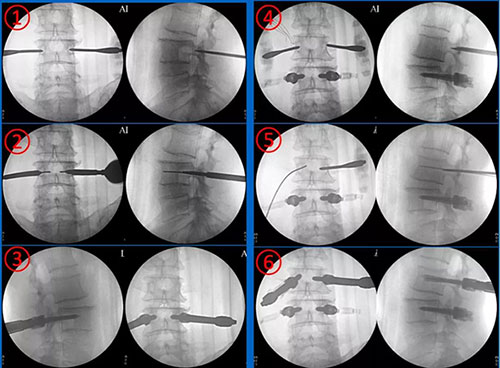

手术过程如下:

穿刺置钉

处理黄韧带,显露神经

置入工作通道,撑开,试模,置入椎间融合器

刀口不用放置引流管